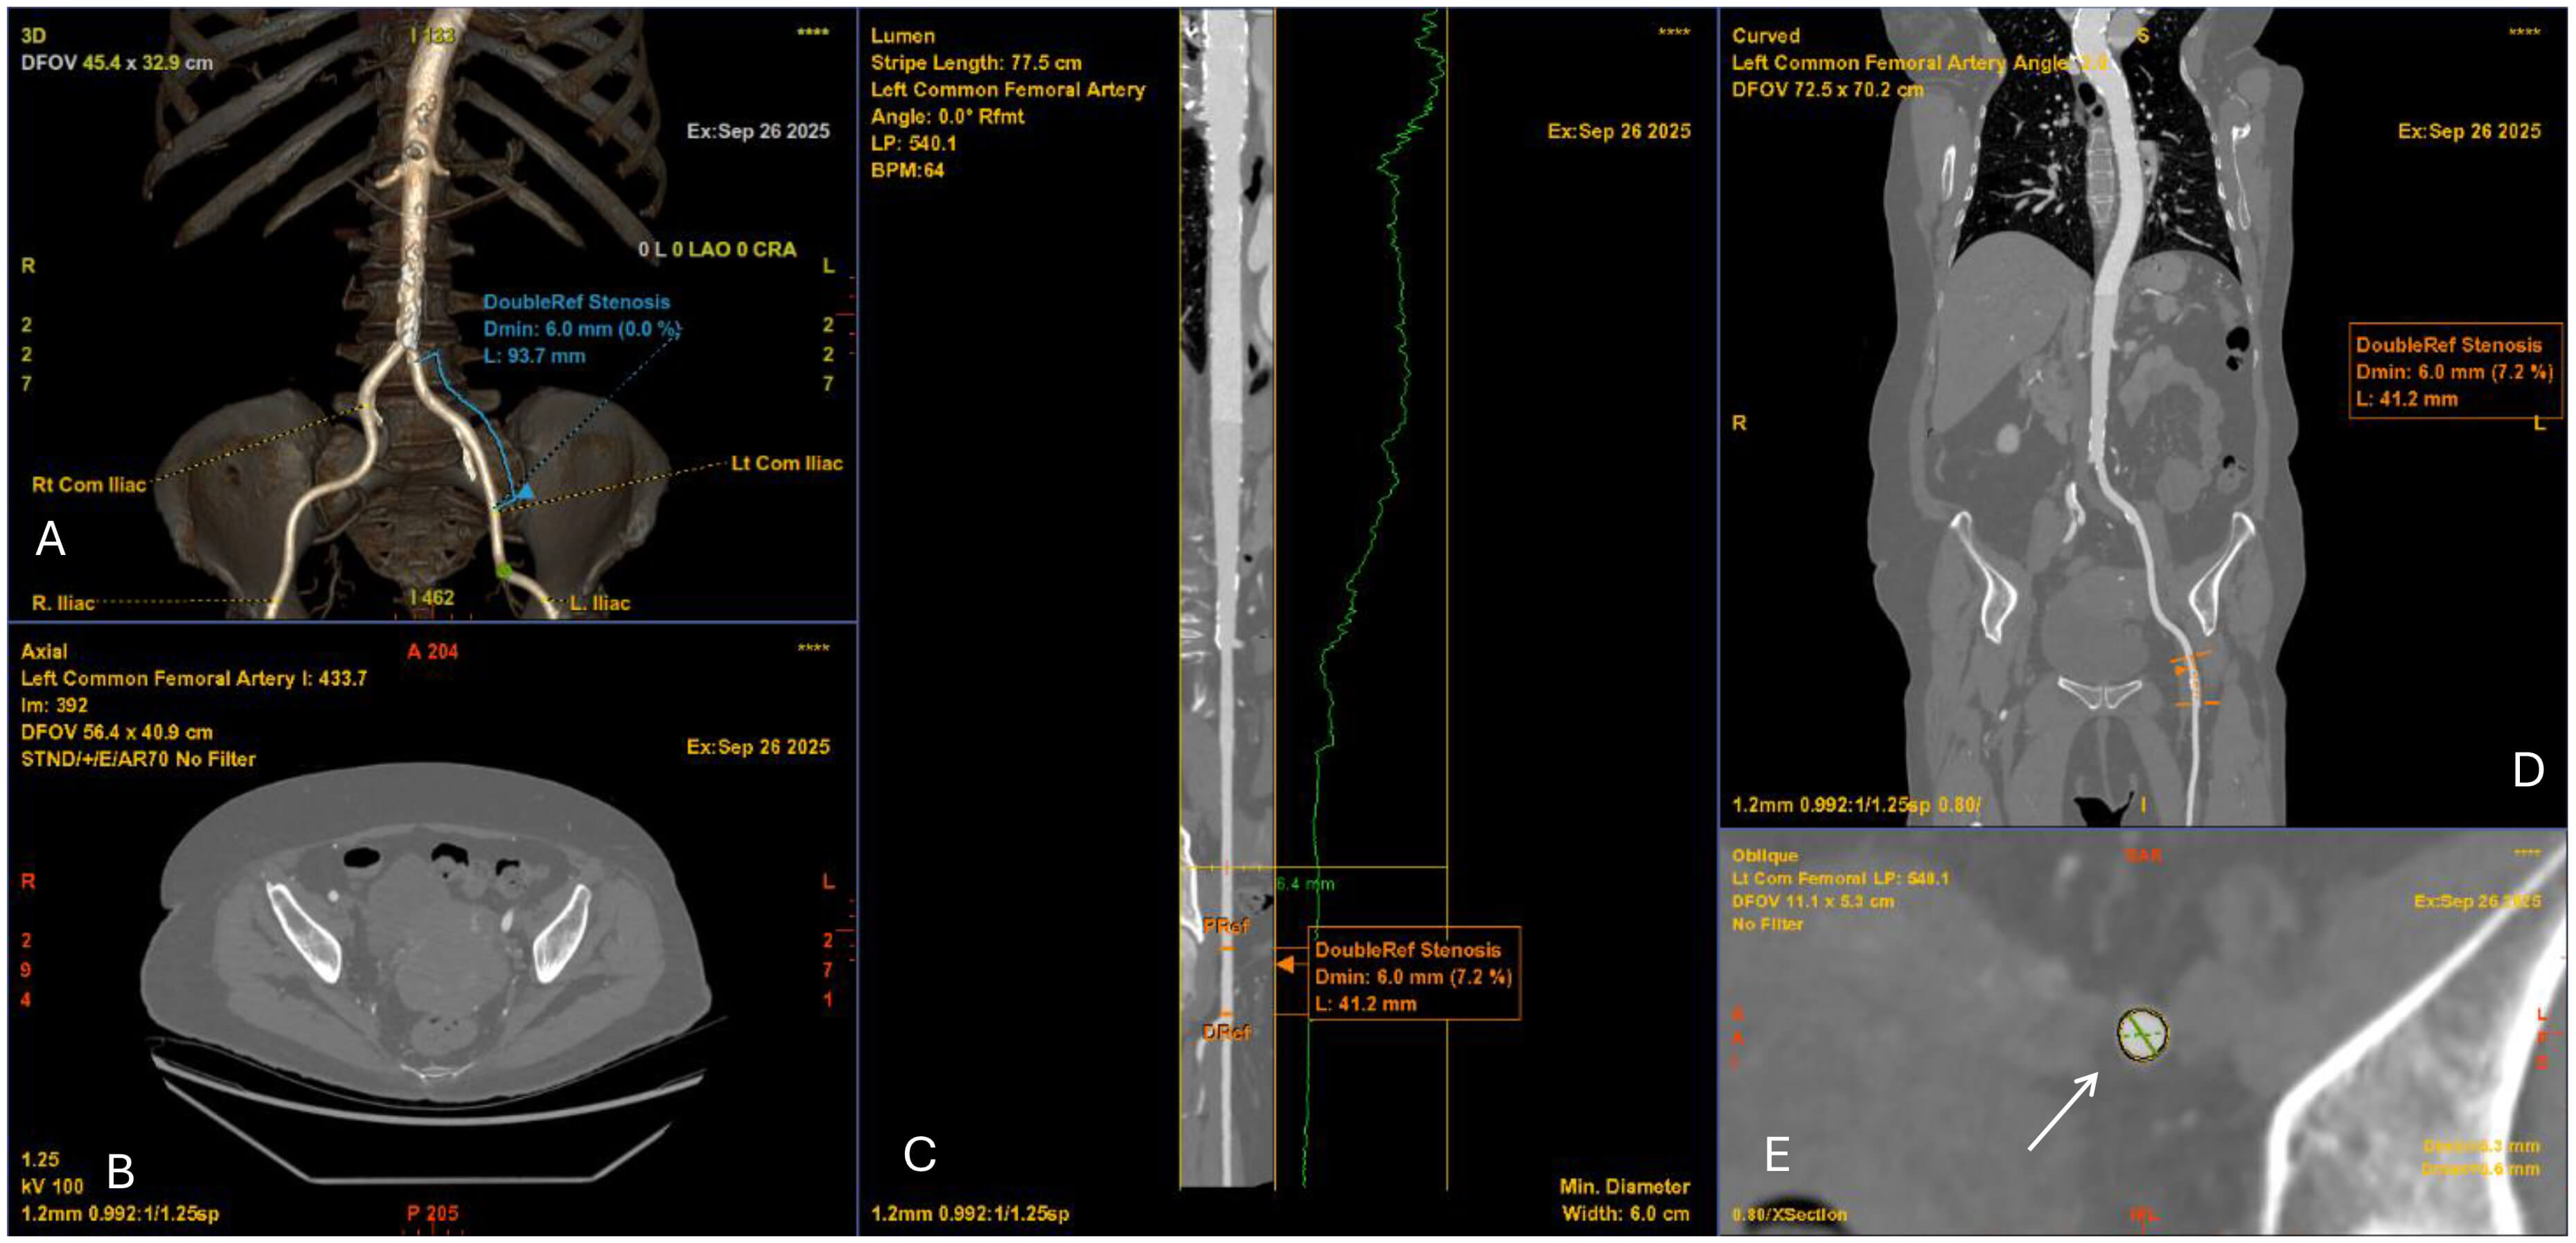

Transfemoral access is preferred for TAVI whenever possible, making careful CT evaluation of the iliofemoral arteries essential [27]. CT provides accurate quantification of luminal diameter, calcific burden, tortuosity, and the presence of stenotic or aneurysmal disease (Fig. 1). CPR and centreline-based analyses should always be used to account for tortuosity [28]. The minimal luminal diameter must be measured precisely. However, vessel suitability is not defined by diameter alone. Other factors such as circumferential calcification and tortuosity, can significantly increase the risk of dissection or perforation, even if the lumen size is adequate [29]. Tortuosity grading further informs procedural planning, as severe angulation can impede sheath advancement [30, 31]. Despite lower-profile delivery systems and improved closure devices [32], thorough vascular evaluation remains necessary to reduce vascular-related complications such as dissection, perforation, or occlusion [33]. When anatomy is unfavourable including small calibre, concentric calcification, or extreme tortuosity, alternative access routes should be considered [34].

Fig. 1.

Computed tomography angiography (CTA) of the iliofemoral vessels for TAVI access planning. (A) 3D volume-rendered reconstruction of the iliofemoral arteries demonstrating vascular course and minimal luminal diameter of 6.0 mm. (B) Axial CTA slice at the pelvic level showing vessel lumen and surrounding structures. (C) Curved multiplanar reconstruction of the left common femoral artery with luminal profile (green line) demonstrating focal stenosis (minimal diameter 6.0 mm). (D) Coronal CTA reconstruction confirming the level of stenosis (6.0 mm). (E) Cross-sectional image at the site of stenosis (white arrow) with measurement of the minimal luminal area, relevant for determining vascular access feasibility.